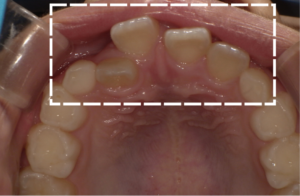

矯正治療中の負担が少ないマウスピース矯正で、大人も・子どもも、歯の寿命延伸にも貢献する良い歯並びを手に入れましょう。豊富な実績と、提携歯科医師らの専門性の高い知識・技術を活かします。